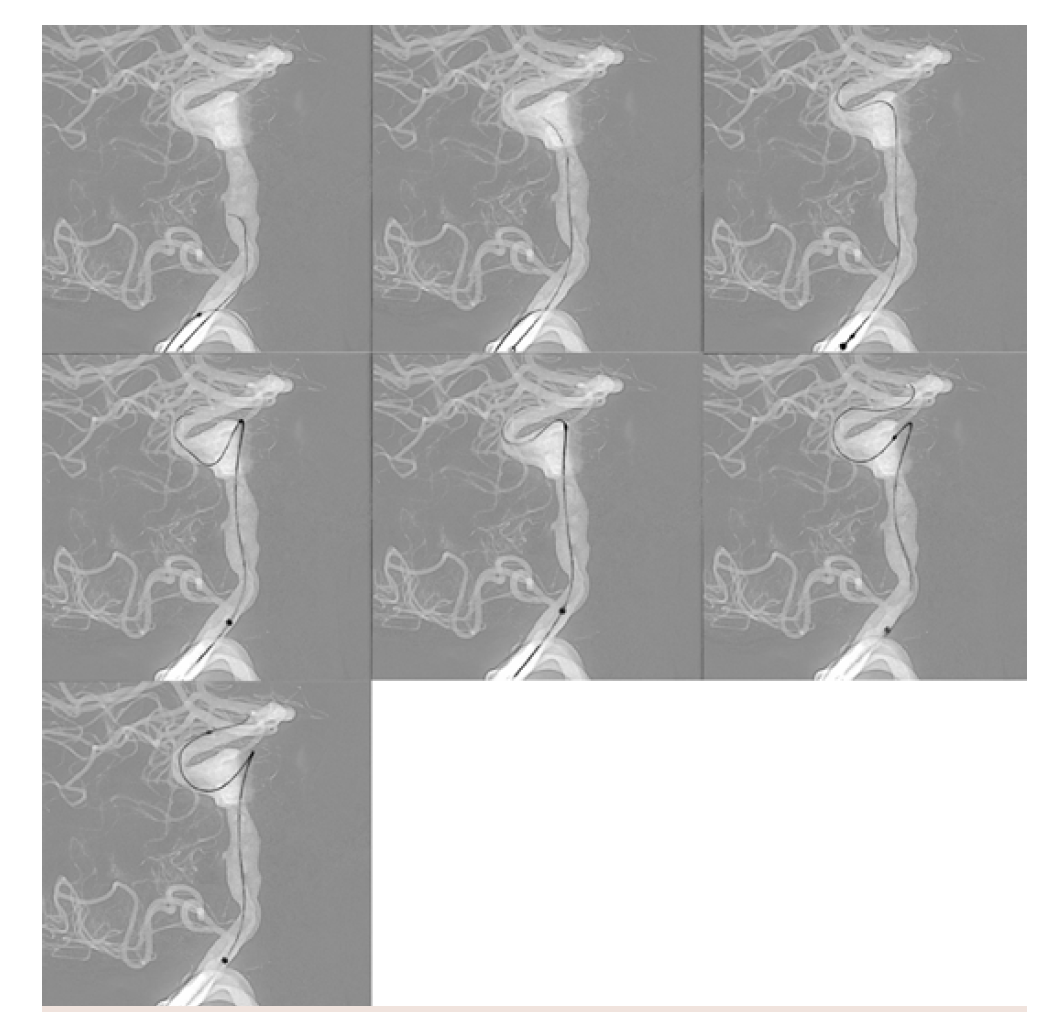

I then line up my working projections using the 3D reconstruction—using the biplane angles determined by the machine in both A and B planes—which is a massive timesaver and will also save on contrast and radiation. The “C arm follows 3D” (Siemens Healthcare AG) function can be utilized to automate the image intensifier and table movement into my selected projections (Figure 4). I typically use either the highest magnification or second highest on each projection. I then do another angiographic run to confirm that these are the appropriate projections and that I have centered my area of interest appropriately and convert these to roadmap images (OPTIQ DSA, Siemens Healthcare AG). The DSA run-to-roadmap conversion enables me to choose the exact frame that I want to use in each projection–an advantage over traditional roadmapping—and it also provides a sharper-appearing roadmap. I can also adjust the radiation usage of the roadmap and even change the radiation usage depending on which part of the case I am doing (catheterization, stent deployment, recapture, etc.), which gives me extraordinary flexibility in the way that I use radiation for the desired tradeoff of radiation usage vs resolution.

I then do the catheterization, which has been aided by the roadmapping feature and how easy it is to see catheters on guidewires on the ARTIS icono. I then deploy the devices, using a single shot as necessary. Next, I remove the microcatheter and perform magnified arteriograms through the support catheter and

Access was quickly obtained using an Aristotle 18 guidewire (Scientia Vascular) (Figure 13). This is the lowest radiation roadmap setting. Note the outstanding visualization of the catheters and wires. In a long, complex, high-risk case, excellent visualization and radiation sparing are 2 major priorities. The ARTIS icono enables both.

The first pipeline stent was aligned tip-to-tip and ready for deployment (Figure 14). Stent visualization is another major strength of the ARTIS icono. If the DSA roadmap feature is utilized, making a roadmap from a frame of an arteriographic run, then switching to a higher-radiation roadmap setting is an option at this point.